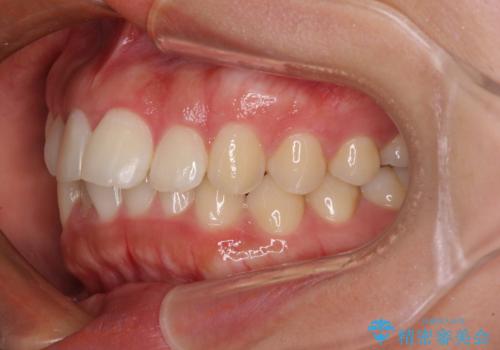

飛び出した上顎前歯 インビザラインで引っ込める

- 前歯の突出感を気にして来院された患者様です。

奥歯の咬み合わせは理想的な咬合に近く、インビザラインでも十分に対応できる歯列でした。

舌の突出癖を改善するためのトレーニングを行いつつ、上下歯列全体を後方に移動させ、更にはIPR(歯と歯の間を削る)によりスペースを獲得することで、口元の突出感を改善することとしました。